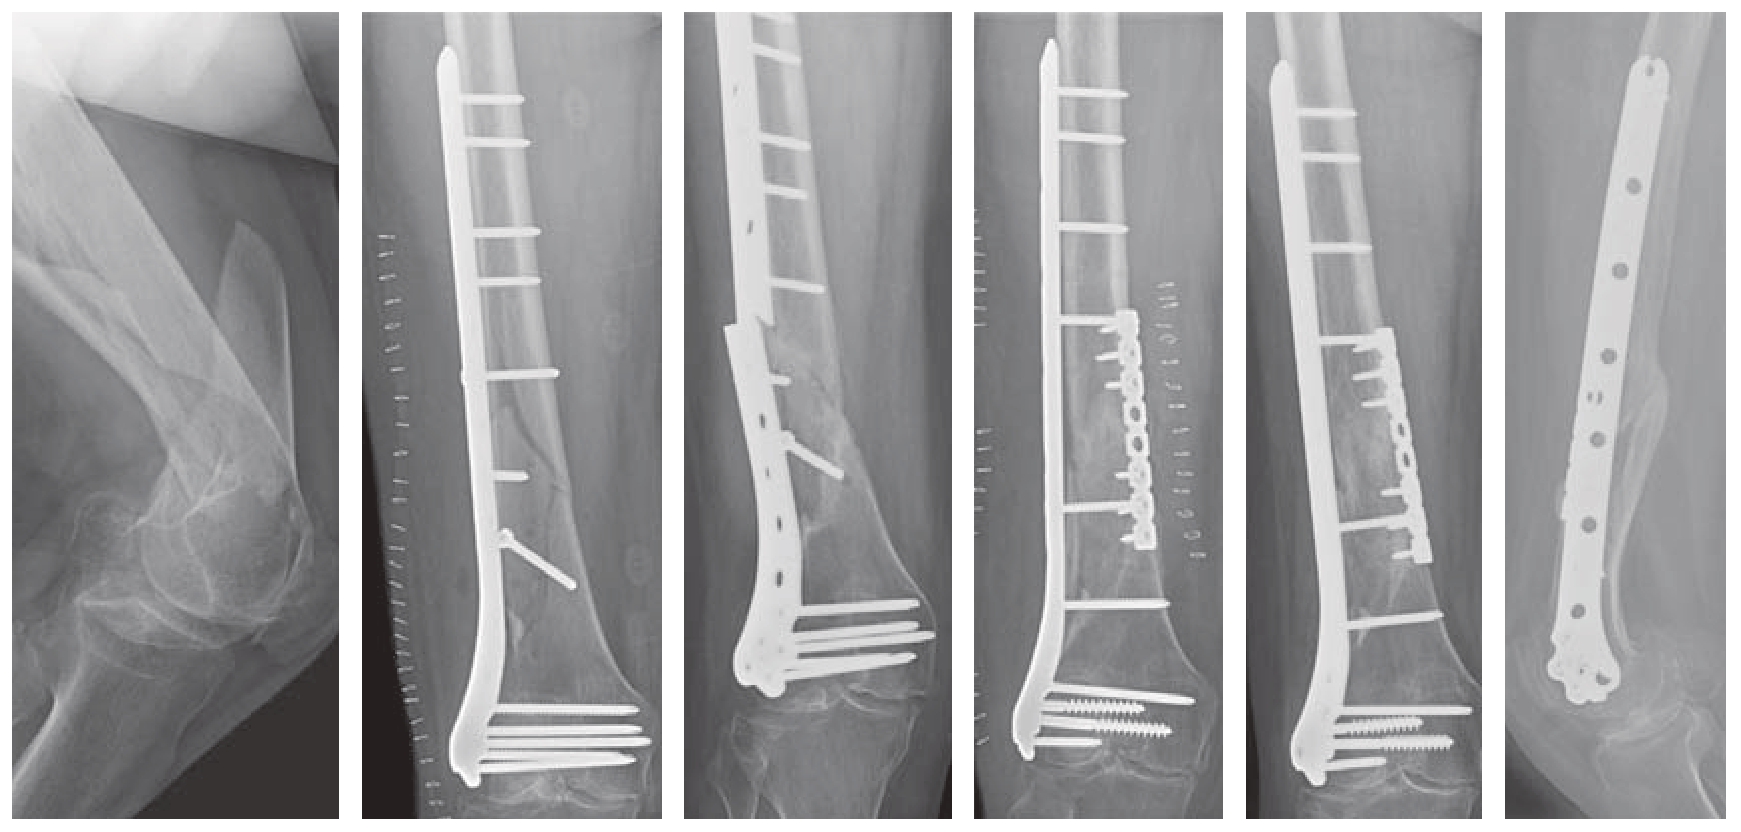

(2)内侧辅助钢板:锁定钢板治疗股骨远端骨折,多置放于股骨的外侧,属于张力侧固定。当骨折为粉碎性骨折、内侧存在蝶形骨块或内侧存在缺损,即内侧股骨髁缺少支撑时,容易发生断板、断钉现象。这时,可考虑在内侧髁添加钢板辅助固定,使固定更牢靠、应力分布更均衡。内侧钢板可选择内侧髁钢板、普通锁定钢板、重建钢板等。重建钢板易塑形,容易操作,临床应用效果良好。内侧添加辅助钢板,在股骨远端骨折翻修术中应用更广(图11—4)。

img

图11—4 股骨远端骨折术后,钢板断裂,返修,添加内侧钢板